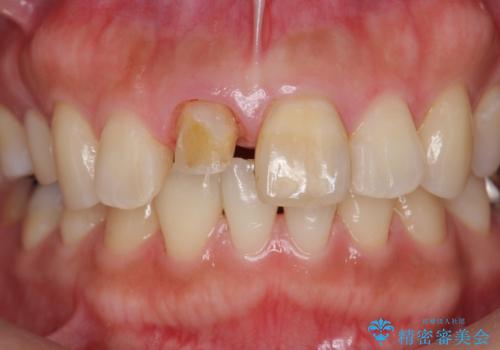

- 歯の神経を除去したのちの、変色の改善を希望され来院されました。

再度根管治療を行ったのちの、オールセラミッククラン治療を計画します。

色調の再現に優れるオールセラミッククラウン スペシャルプランでの治療を希望されました。(保証5年間)